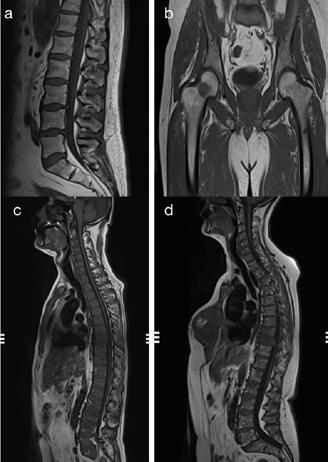

Patternuri de infiltrare a măduvei osoase în MM decelate prin IRM (figura )

Leziunile MM sunt prezente predominant în scheletul axial și anume vertebre (66%), pelvisul osos (30%) și într-o măsură mai mică la nivelul scheletului extra-axial (coaste, schelet apendicular) [20] În literatură sunt descrise cinci tipuri de infiltrare a măduvei osoase în mielomul multiplu: măduvă cu aspect normal, infiltrare focală a măduvei osoase, infiltrare difuză, infiltrare de tip “sare și piper” și infiltrare combinată focală și difuză [21, 22]; Există o multitudine de studii apărute în literatură care corelează aceste tipuri de infiltrare medulară cu modificările vizualizate la examenele morfo-patologice [23, 24]. În majoritatea cazurilor de MM (28%) se observă un aspect normal al măduvei osoase, cu hipersemnal T1 omogen al acesteia; în cazul infiltrarii, focale se observă diverse leziuni focale T1 hipointense, care pot apărea oriunde la nivelul scheletului; în cazul infiltrării difuze, se observă hiposemnal T1 difuz la nivelul intregii măduve osoase, uneori în caz de infiltrare severă, semnalul fiind chiar mai redus decât cel al discului intervertebral. În doar 3% din cazuri se observă un model de tip „sare și piper” și în 11% din cazuri se poate observa un model mixt de infiltrare nodulară și difuză [22, 25]

Tipuri de afectare medulară în mielomul multiplu: aspect normal imagistic(a), infiltrare focală(b), infiltrare difuză(c) infiltrare de tip ‘sare și piper’, infiltrare mixtă de tip focal și difuz(d). Departamentul de Radiologie al Spitalului Clinic Municipal de Urgență - Timișoara/RO